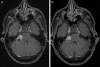

Bilateral vestibular schwannomas are the hallmark of neurofibromatosis type 2 (NF2), and these tumors impair hearing and frequently lead to deafness. Neurosurgical intervention, the only established treatment, often damages the vestibular nerve. We report 2 cases in which treatment with bevacizumab (for 3 months in one case and 6 months in the other) induced regression of progressive vestibular schwannomas by more than 40% and substantially improved hearing in the patient treated for 6 months. Bevacizumab therapy may thus provide an effective treatment for progressive vestibular schwannomas in patients with NF2.